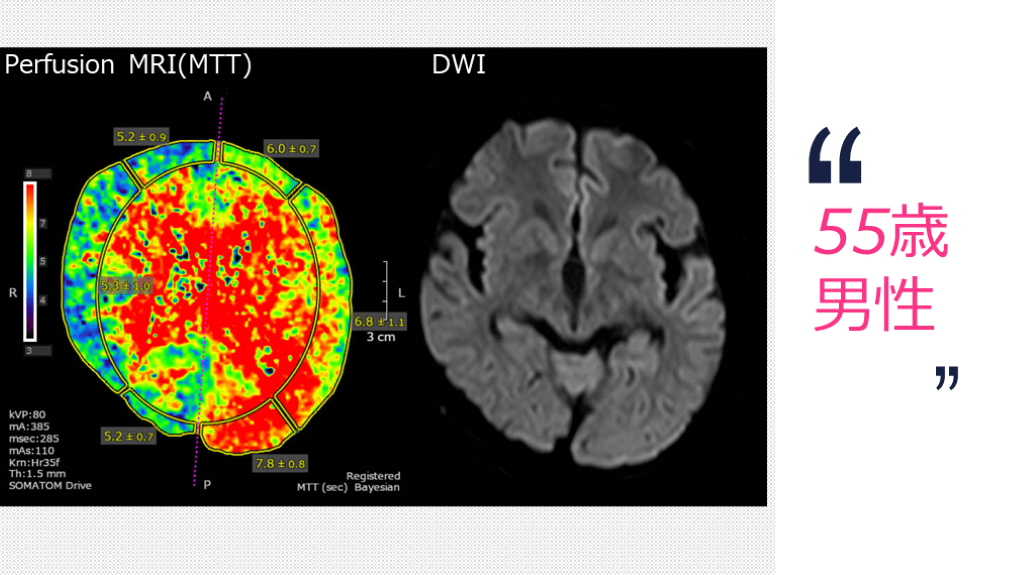

55歳 男性 Perfusion MRI(MTT) DWI